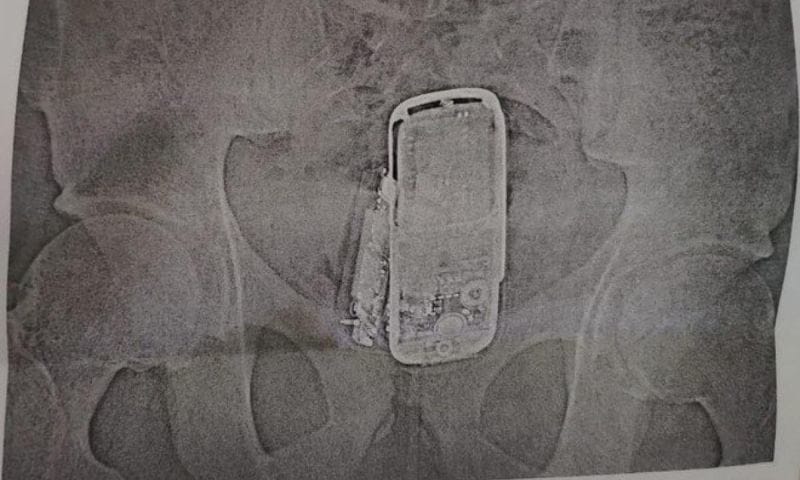

ロシアにて、刑務所に面会にやって来た18歳の少年を不審に思った看守が少年を調べると、お尻の辺りから金属探知機の反応が…。その後肛門の中から、3つの携帯電話、バッテリー、充電ケーブルなどが発見されたとの事。面会相手であった兄にこっそりと渡すつもりだったようだ。X線写真など。(※ TOP画はイメージ)[2]images